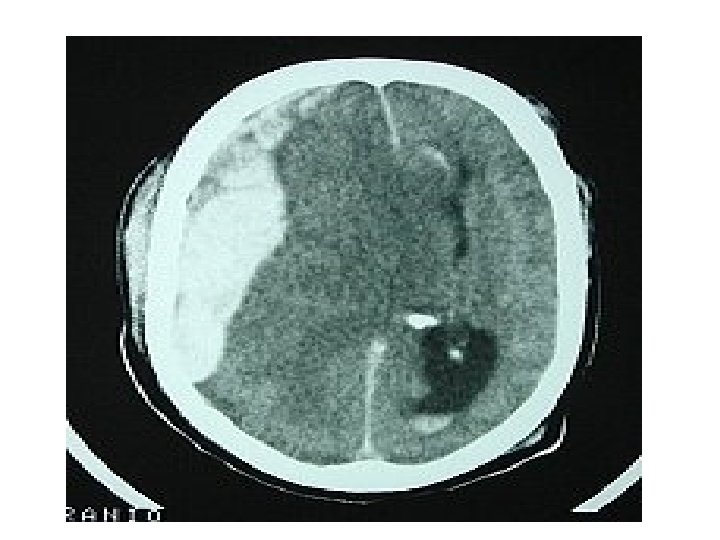

Traumatic Intracerebral hematoma